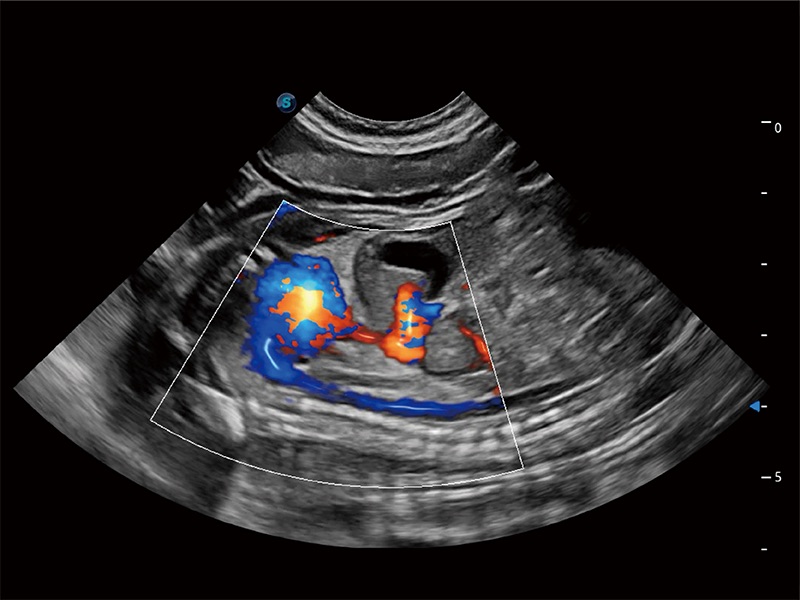

优异的基础图像

ProPet 80 全新的动物超声智能软件和丰富的探头群,为动物医生提供了高清晰度和精细分辨率的图像,无论在宠物、马科、畜牧还是实验室动物等应用中都可以轻松应对,为您的日常工作带来满意的体验。

(犬)胎儿主动脉弓立体血流

• Bright Flow 立体血流成像

在传统二维血流成像的基础上,呈现血流的立体感,具有动感的生命力之美。即便是微小的血管也能轻松应对,提高了血流的视觉敏感性。